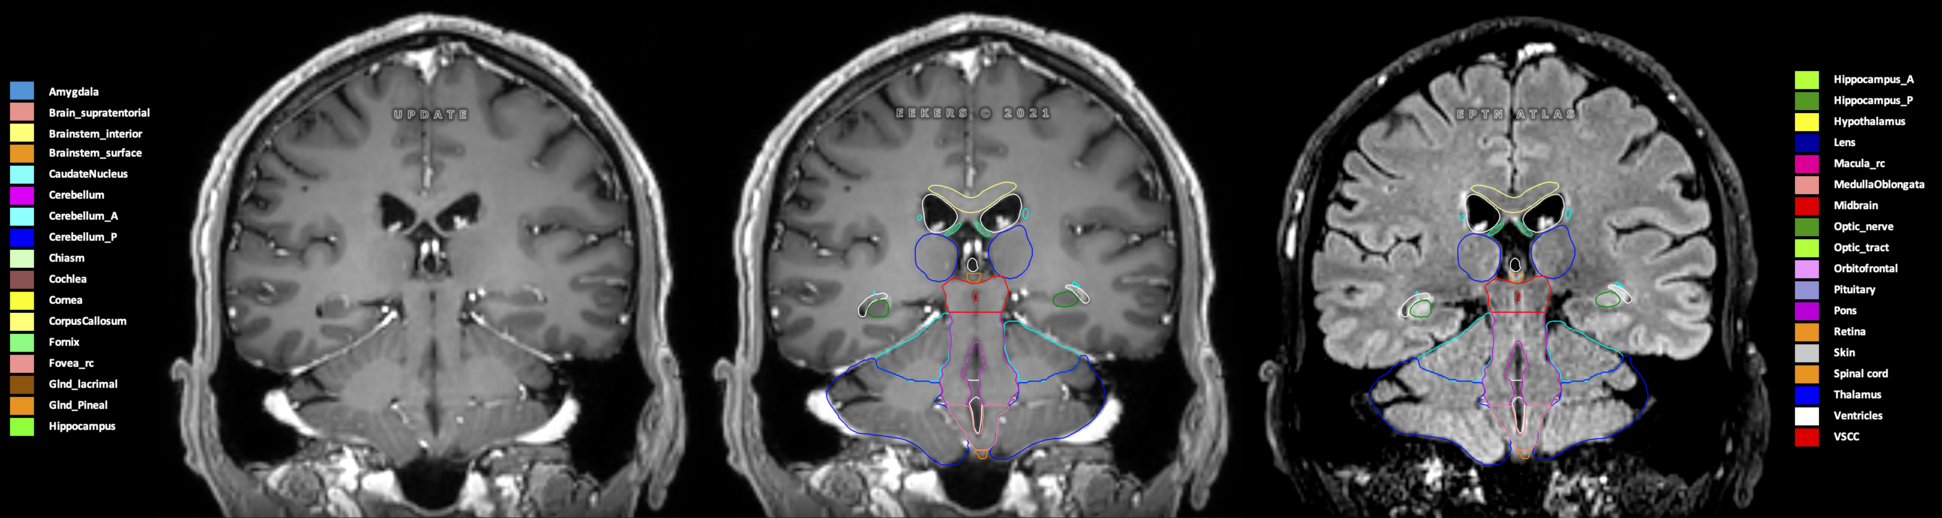

Eekers et al. have published an international neurological atlas for contouring of organs at risk in consensus with the European Particle Therapy Network (EPTN) in 2018 and an update in 2021. The purpose of this consensus atlas is to decrease inter- and intra-observer variability in delineating OARs relevant for neuro-oncology.

Included are all OARs known to be relevant for radiation-induced toxicity in neuro-oncology: brain, brainstem (midbrain, pons, medulla oblongata), chiasm, cerebellum (anterior & posterior), cochlea, cornea, hippocampus (anterior & posterior), hypothalamus, lens, lacrimal gland, optic nerve, pituitary, skin, and vestibular & semicircular canals. To further facilitate research on cognition, vision and radiological changes after irradiation of the brain, potential clinically-relevant OARs are included: amygdala, caudate nucleus, cerebellum (anterior & posterior), corpus callosum, fornix, macula, optic tract, orbitofrontal cortex, periventricular space (PVS), pineal gland, and thalamus.

Three-dimensional delineation of the 25 consensus OARs for neuro-oncology are shown on CT (WW/WL 120/40, 3000/600), 3T MR images, (T1Gd, T2FLAIR 1mm) and 7T MR (MP2RAGE 0.7 mm). All are presented in transversal, sagittal and coronal view.